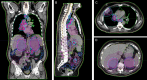

Current treatment paradigms for oligometastatic non-small cell lung cancer (NSCLC) utilize systemic chemotherapy alone or in combination with immune checkpoint inhibitors (ICIs). The addition of ICIs in NSCLC has led to significant improvements in survival; however, recurrence remains common. New methods are needed to enhance anti-tumor immune responses and improve patient outcomes. Here, we present the first case of utilization of the Ethos OART platform to deliver multi-site pulsed hypofractionated radiotherapy in a patient with oligometastatic disease on the single arm prospective clinical trial SiCARIO (Split-Course Adaptive Radioimmunotherapy in Oligometastatic NSCLC, NCT05501665). A 67-year-old man with stage IV NSCLC with metastases to bilateral adrenal glands, retroperitoneum, and mesentery was prescribed treatment of 40 Gy in 5 fractions on SiCARIO in combination with SOC chemoimmunotherapy. A multi-target single isocenter approach was utilized to treat nine distinct targets in five total isocenters. Treatment plans were generated using an isotopic approach prioritizing organ at risk (OAR) constraints with the goal of minimum coverage of at least 30 Gy in 5 fractions. CBCT was acquired with each fraction to generate new targets and OAR contours based on anatomic changes with the patient on the treatment table. A comparison of an adapted plan to a base plan was performed online with a selection of superior plans based on target coverage and OAR constraints. The adapted plan was deemed superior for all but 1 fraction of a single isocenter for this patient. The discussion will focus primarily on the bilateral adrenal isocenter, where bulk tumor shrinkage of greater than 80% was observed in this patient with corresponding significant dosimetric benefits. This case demonstrates a potential clinical benefit of OART in multi-metastasis RT. Further data is needed to confirm the safety and efficacy of this approach. Enrollment is ongoing.